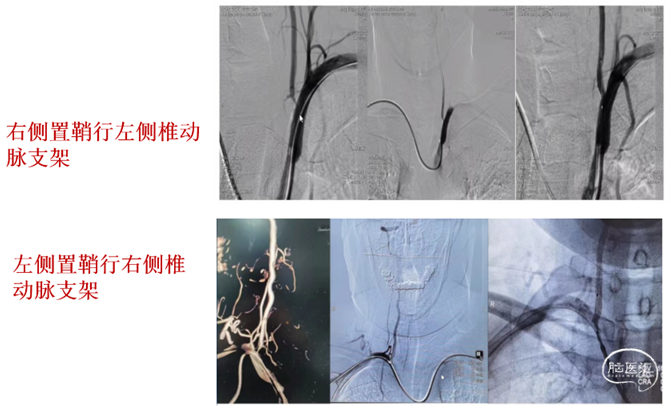

(一)低位椎动脉狭窄经绕对侧入路支架置入

1、椎动脉狭窄,如果开口向内侧,行同侧桡动脉入路时角度不顺行,存在支架通过困难,回撤球囊时支架出现移位或撤出困难。

2、可选择对侧桡动脉置入6F动脉鞘,单弯或西蒙导管将0.035泥鳅导丝置于病灶侧锁骨下动脉起到牵拉作用。

3、将6F导引导管到达狭窄椎动脉附近,微导丝导引球囊扩张支架(4-5mm)铆定狭窄部位后扩张释放支架。

备注:6F导引导管可兼容0.035 in泥鳅导丝和球囊扩张支架(4-5mm),5mm支架通过略涩。

经对侧桡动脉置6F动脉鞘,行对侧低位椎动脉支架置入示意图: